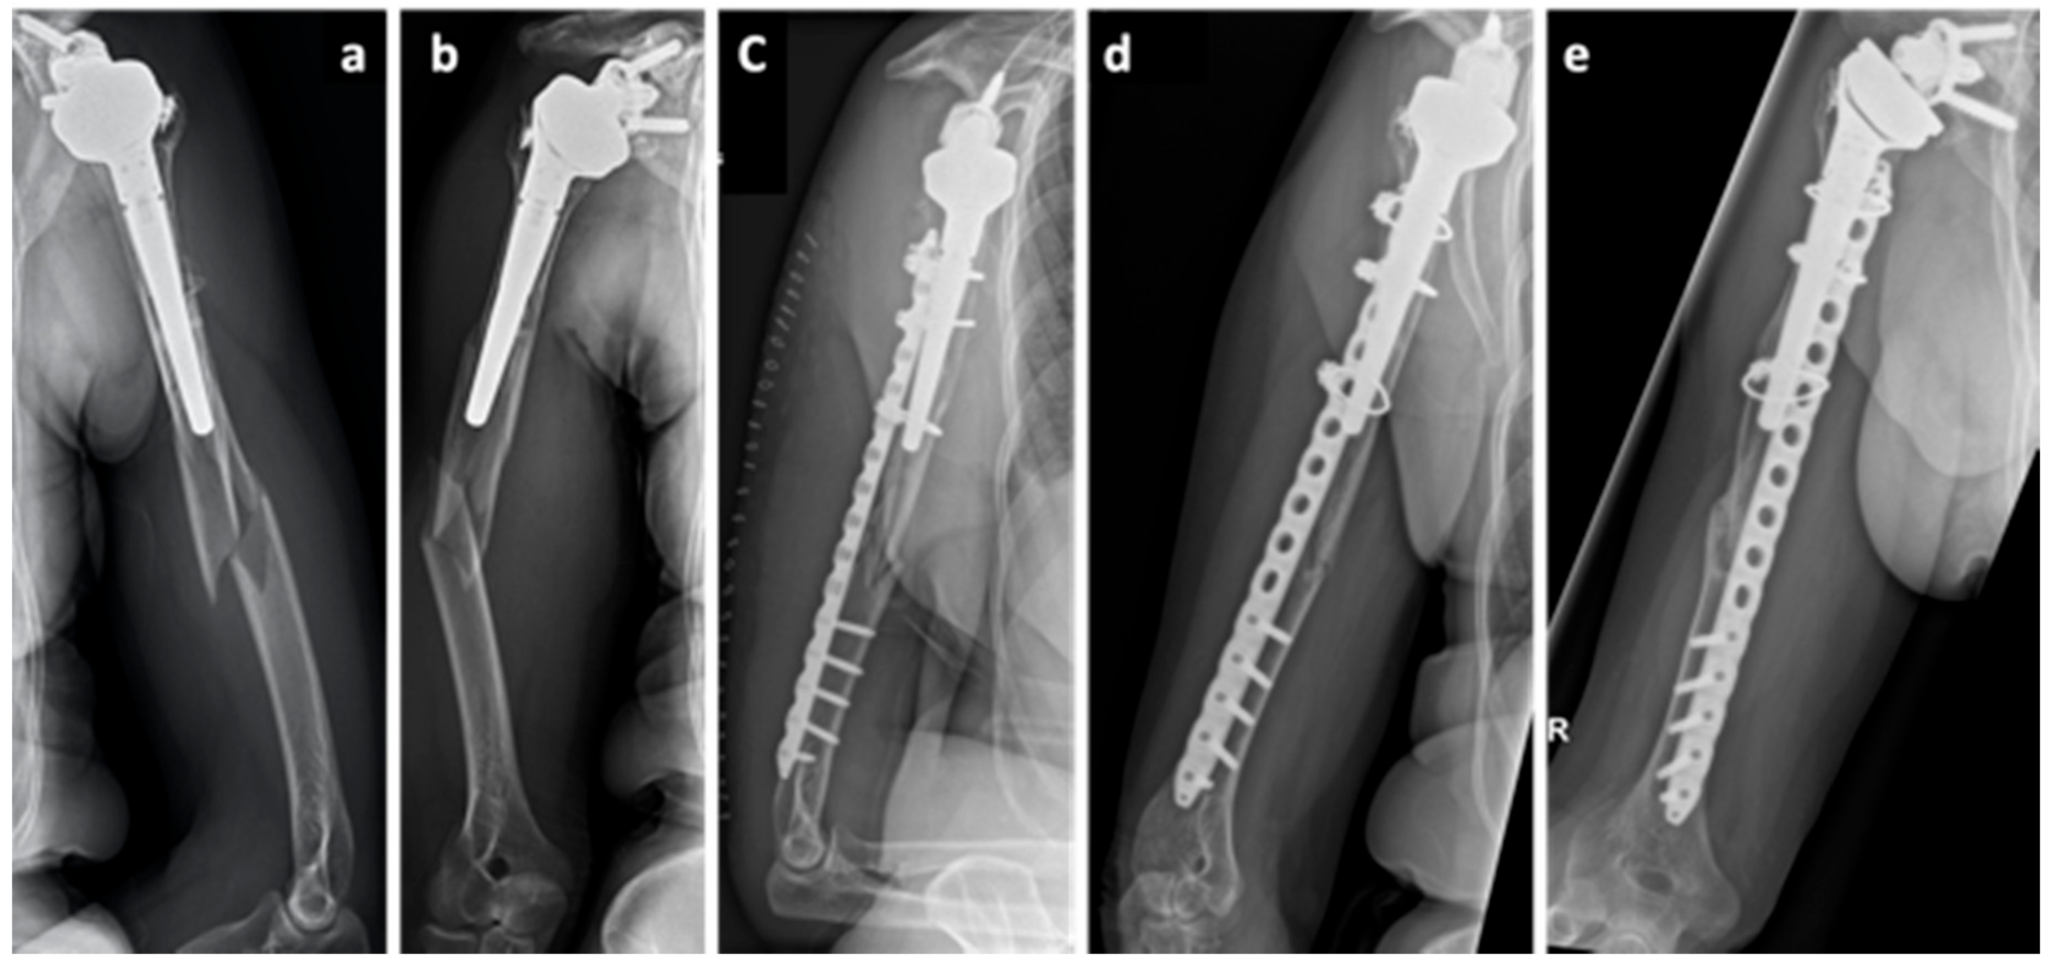

2. Case Series